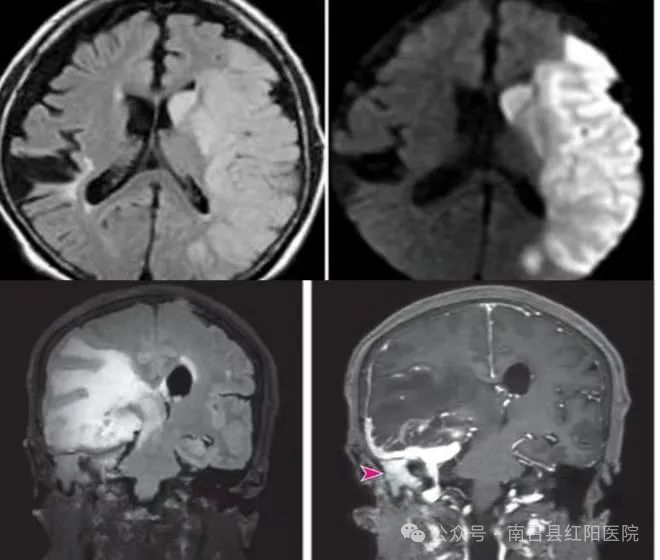

放射科检查是利用放射线对人体内部结构进行成像的一种医学检查方法。这些检查包括X射线、CT(计算机断层扫描)、MRI(核磁共振成像)等。通过放射科检查,医生可以观察人体内部的器官、组织、骨骼等结构,从而诊断疾病或评估病情。X射线检查:X射线是一种能穿透人体的电磁波,它可以使人体内部的组织结构在胶片或数字屏幕上显示出来。X射线检查通常用于检查骨折、肺炎、肺结核等疾病。CT检查:CT即计算机断层扫描,它利用X射线旋转扫描人体,然后通过计算机处理生成三维图像。CT检查具有较高的分辨率,可以清晰地显示人体内部的组织结构,常用于肿瘤、脑血管病变等疾病的诊断。MRI检查:MRI即核磁共振成像,它利用磁场和射频脉冲使人体内的氢原子发生共振,从而生成图像。MRI检查对软组织具有很高的分辨率,常用于脑部、脊柱、关节等疾病的诊断。